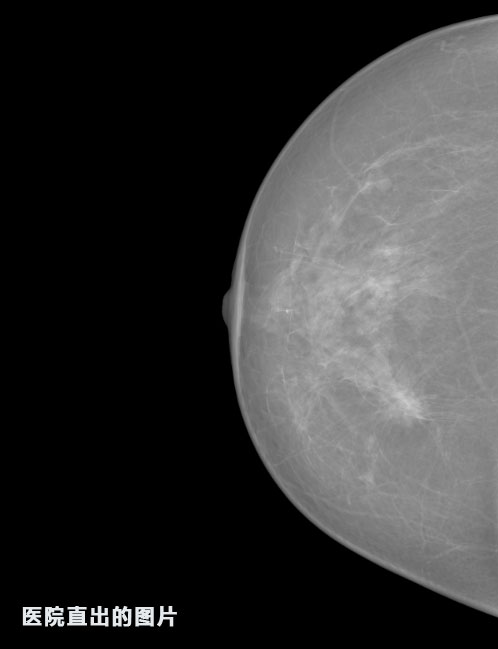

識別報告:

1.發(fā)現(xiàn)良性鈣化,可能性為19.88%---位置框指數(shù):[1796.0867 1359.8237 2058.1372 1582.5334]

2.發(fā)現(xiàn)惡意鈣化的可能性為15.18%---位置框指數(shù):[1789.4733 1365.9951 2063.7698 1576.0613]

3.發(fā)現(xiàn)惡意鈣化的可能性為12.45%---位于框指數(shù):[1859.3987 1422.3184 2006.5494 1528.2698]